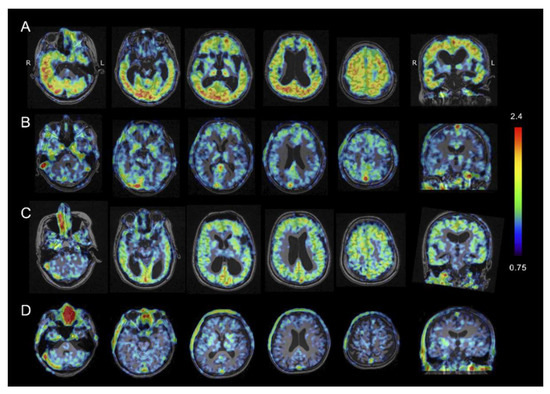

2.4. Amyloid β PET Imaging